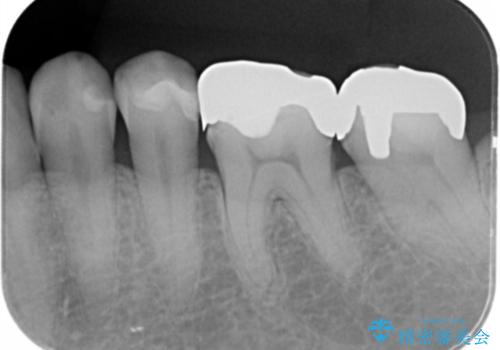

- 「長年使っている奥歯の目立つ銀歯を白くしたい。」、と希望され来院されました。

銀歯を丁寧に除去し、このように銀の覆っている面積が多い場合は、インレータイプではなくより強度に優れ歯もセラミックも長持ちするジルコニアクラウンでの治療を計画します。

- 26.4万円(ジルコニアクラウン×2・仮歯×2)費用は治療当時の料金となります